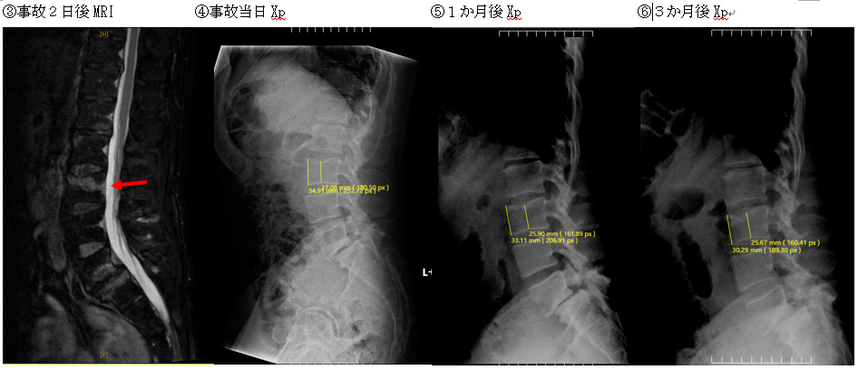

例えば、下記画像の第3腰椎は、事故当日に撮影されたXp上(画像④)、前縁椎体高34.91㎜、中央椎体高27.08㎜だったのが、事故3か月後には(画像⑥)前縁椎体高30.29㎜、中央椎体高25.67㎜まで減少しています。

なお、この方は自賠責の1度目の認定で11級7号の認定を受けています。

下記画像③では、MRI画像上、第3腰椎椎体上方に輝度変化が生じており、圧迫骨折が進行する骨挫傷が生じていたことがわかります。